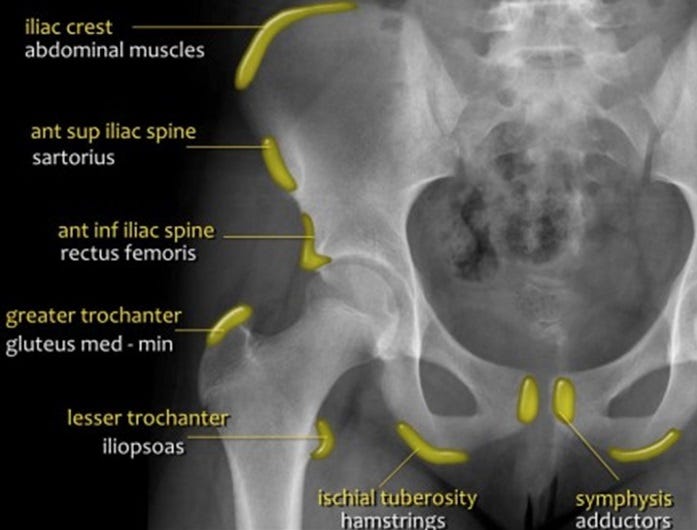

Avulsion injuries of the pelvis are a frequent cause of hip pain in adolescents involved in sports. Because at this age the tendons are generally stronger than the apophyses, strong muscle contraction can result in apophyseal avulsion fractures (Fig.6). Avulsion injuries can be acute or chronic.

Figure 6. Sites of common avulsion injuries and muscle attachments.